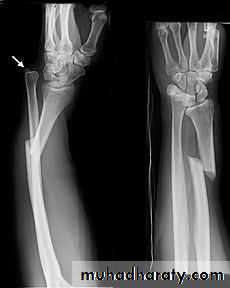

Fall on out stretched hand

Hand deformity